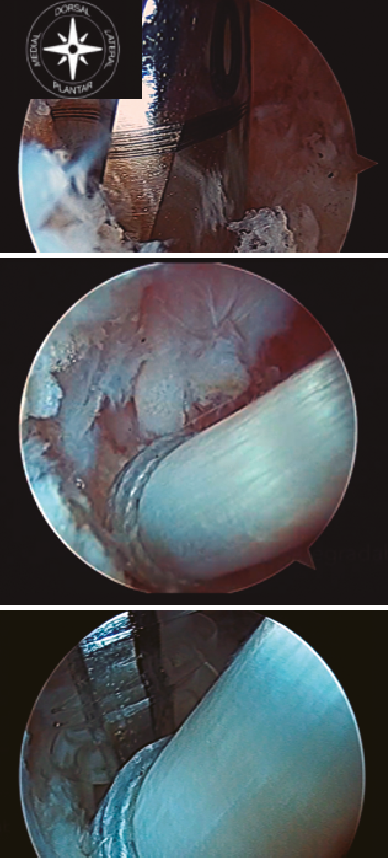

Posteriormente, debemos realizar el túnel ciego en el calcáneo. El lugar idóneo de inserción del FHL sería en una posición central y lo más posterior posible de la tuberosidad posterior del calcáneo, si bien es cierto que, en ocasiones, dependerá de la longitud obtenida de tendón del FHL. Para ello, se utiliza una aguja guía de Kirschner con un ojal para poder labrar el túnel en el calcáneo. La aguja de Kirschner se introduce en el calcáneo en una dirección dorsal-medial a plantar-lateral. El diámetro adecuado de la perforación depende del diámetro del tendón FHL medido. Generalmente será 0,5-1 mm mayor al tamaño de la plastia (Figura 4).

Figura 4. Túnel ciego en la tuberosidad posterior del calcáneo. Introducción de la plastia y fijación con tornillo de biotenodesis.

Como mínimo, se debe introducir de 10 a 15 mm de la plastia obtenida. Una vez realizado el túnel, se introduce una sutura en el ojal de la aguja de Kirschner y traccionamos de la aguja desde plantar para poder pasar las suturas a través del túnel labrado y así poder introducir el tendón en el interior del túnel. Posteriormente, con el tobillo en flexión plantar, se tracciona de las suturas para tensar el tendón del FHL bajo visión artroscópica directa, con el fin de obtener una tensión adecuada de la plastia, y se fija con un tornillo de biotenodesis del mismo tamaño o 1 mm más ancho que el túnel del calcáneo realizado (Figura 4).

Las incisiones cutáneas se suturan y se coloca una férula de yeso suropédica posterior con 15-20° de flexión plantar.